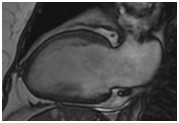

正常心肌

心肌灌注(病例-心肌梗死)